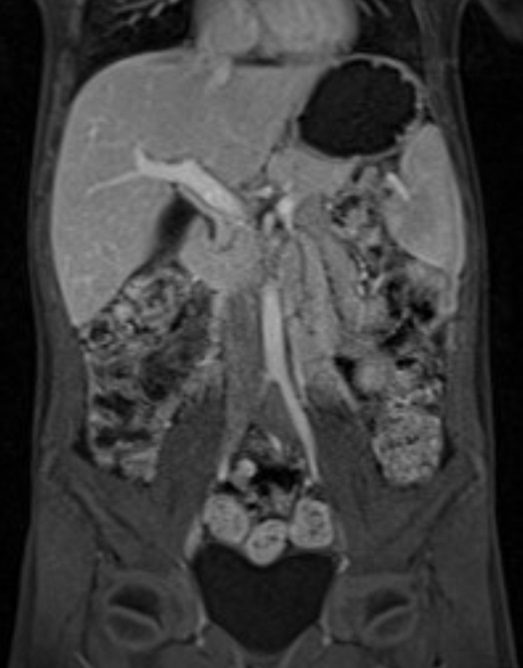

Colangiorresonancia magnética.

Posteriormente se completa estudio con una colangiorresonancia magnética que no es concluyente.

Hígado de morfología normal, contornos lisos e intensidad de señal homogénea, sin lesiones focales definidas. Vía biliar intrahepática de morfología y calibre normal. Conducto hepático común de 4 mm y colédoco de 5,5 mm. No se observan imágenes de defecto de repleción. Vesícula biliar distendida, sin evidenciar lesiones patológicas. Páncreas, bazo (12 cm), glándulas suprarrenales y riñones sin alteraciones valorables.